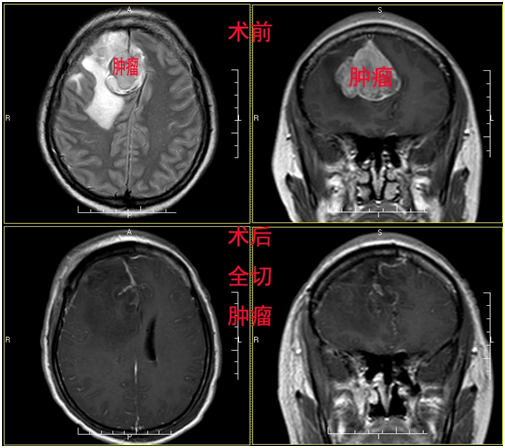

梁女士,44岁,某公司中层管理者,工作非常繁忙,正当她准备在工作上大展拳脚的时候,突如其来的头痛让她烦躁不安。由于每天加班到深夜,回家后倒头就睡,让她无暇关注自己的身体。因为头痛在休息时可以得到缓解,梁女士就没有在意,忙完生意后才抽出时间到医院进行身体检查。这一查不打紧,检查结果着实把梁女士吓丢了魂。原来梁女士的脑子里长了一个大瘤子,头痛就是因为瘤子压迫脑组织引起的。2015年10月开始出现发作性头痛,持续2月,为求进一步治疗入住我院,入院诊断:矢状窦旁脑膜瘤。体查未发现明显阳性体征,排除手术禁忌症,予以手术切除肿瘤组织,头痛症状缓解,术后病理检查提示:混合型脑膜瘤(I型)。